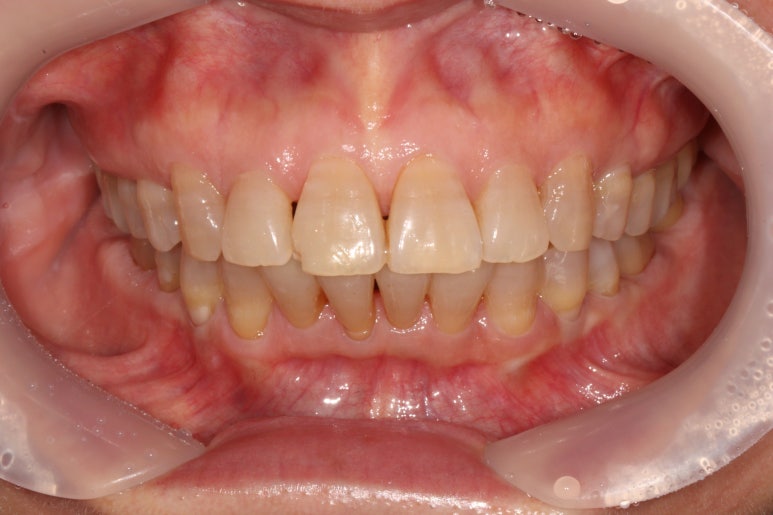

앞니가 좀 삐뚤어져 있었습니다.

보통 아래 앞니보다는 위 앞니가 삐뚤빼뚤 할 때 상담차 오시곤 하는데요,

아무래도 환자의 대부분이 성인이다보니 그런 것 같아요.